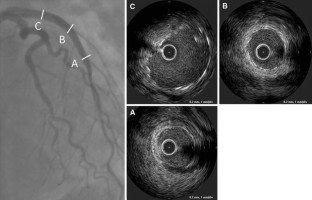

A 35-year-old woman was admitted to our hospital because of a sudden cardiac arrest caused by an acute anterior myocardial infarction. Emergency coronary angiography showed total occlusion of the proximal left anterior descending artery (LAD). We performed an intravascular ultrasound (IVUS) to detect the LAD orifice and successfully inserted the guidewire to the occluded LAD. An IVUS revealed coronary dissection and no atheromatous plaque from the orifice to the mid-portion of the LAD and the guidewire was in the true lumen. Two bare metal stents were implanted in the proximal and mid portion of the LAD. After stenting to the LAD, coronary dissection retrogradely extended to the left circumflex artery (LCx). Therefore, we performed additional stent implantation from the left main trunk (LMT) to the proximal LCx and the just proximal LAD. An IVUS guided percutaneous coronary intervention (PCI) enabled complete revascularization to spontaneous coronary artery dissection.

Fig. 1